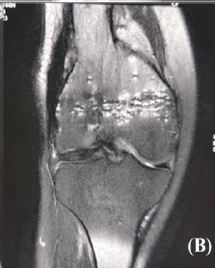

Simultaneous Anterior Cruciate Ligament Avulsion Fracture with Bilateral Posterior Meniscal Root Tears of the Knee: A Case Report

Deem Alsedais , Bader Majed Aljadaan , Hamad H Aldakhil Allah , Abdullah Adel Al-Nasser , Ibrahim Ababtain ………………………………p.222-226